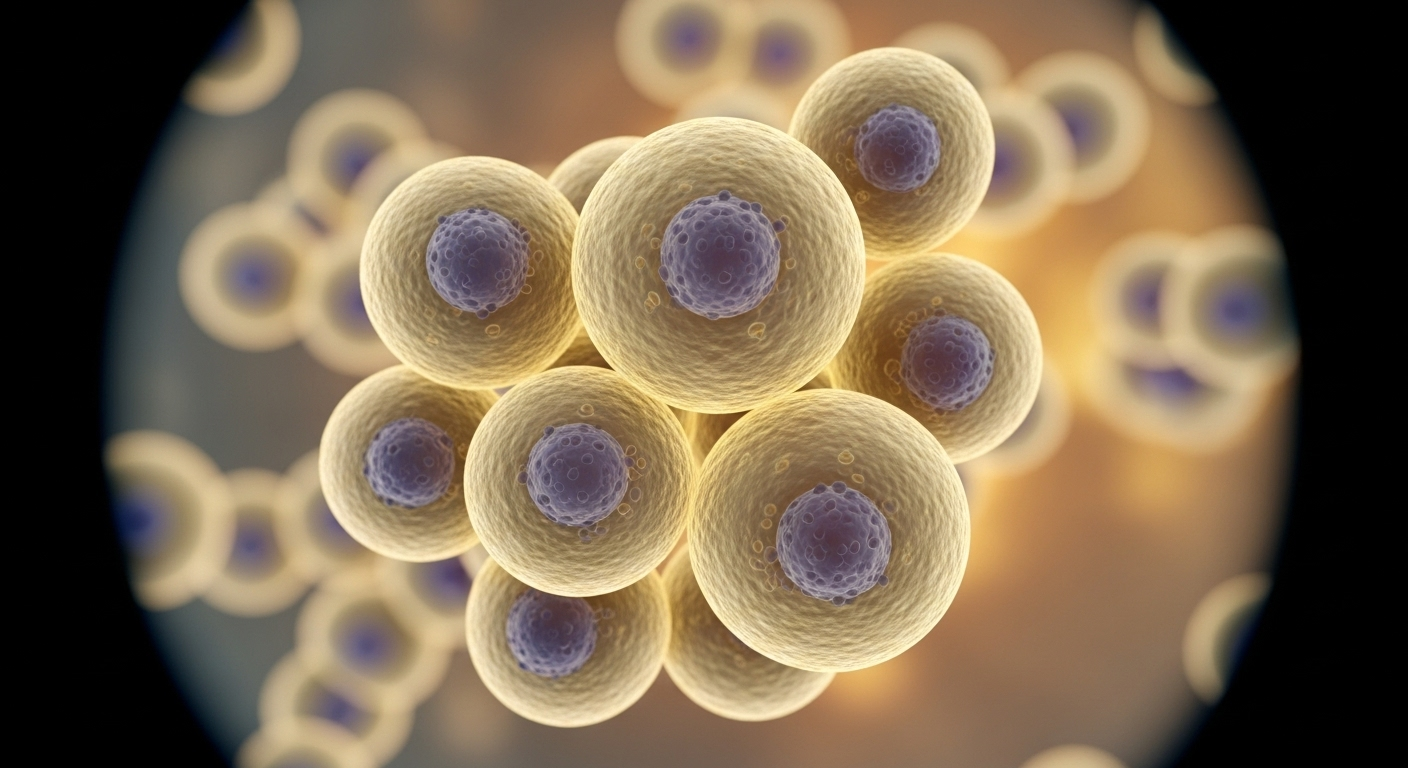

Un outil logiciel aide les scientifiques à analyser des données spatiales complexes dans les tissus sains et malades

Heureusement, des chercheurs de plusieurs grands centres médicaux américains ont trouvé une solution. Ils ont créé un logiciel, une sorte de programme informatique intelligent, pour aider les scientifiques à lire et comprendre ces cartes compliquées de notre corps. C’est une grande nouvelle pour la recherche sur des maladies comme le cancer ou Alzheimer.

Mais voilà le hic : la quantité d’informations est gigantesque. C’est comme passer d’une simple carte de France à une photo satellite de la Terre entière, où l’on verrait chaque maison. Le plus dur n’est plus d’obtenir l’image, mais de **comprendre ce qu’on regarde**. C’est là que le bât blesse. Les biologistes avaient besoin d’un coup de main pour ne pas se noyer dans cette mer de données.